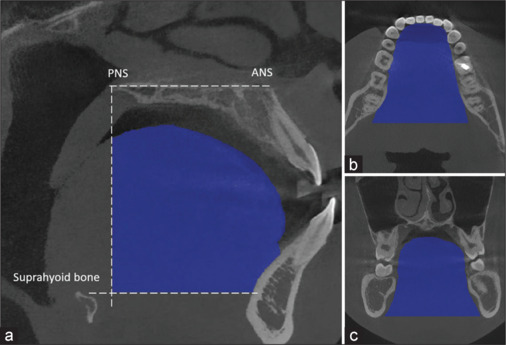

Material and methods: A cross-sectional descriptive prospective study analysis was conducted on 120 patients with varying skeletal patterns who sought examination and treatment at the Department of Dentistry and Maxillofacial Surgery, Can Tho University of Medicine and Pharmacy Hospital. Imaging data from these patients were used to evaluate the volume of the tongue and pharyngeal airway in adults with different malocclusion conditions.

Results: The average volumes of TV (Tongue volume) and TPV (Total pharynx volume) in Class III malocclusion were the largest, with values of 57820.86 cm3 and 28385.33 cm3, respectively. In contrast, the smallest volumes were observed in Class II, with values of 50380.48 cm3 and 23414.58 cm3, respectively.

Conclusions: An inverse correlation has been established between the TV/OCV (Tongue volume/Oral cavity volume) ratio and pharyngeal airway volume. This finding suggests that tongue volume, oral cavity volume, and their ratio influence airway patency. Understanding the relationship between the tongue and the airway in orthodontic treatment planning, particularly in improving airway space for patients with Class II malocclusion.